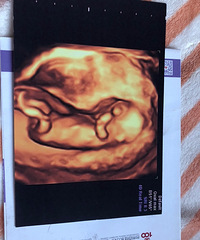

第一次握着小手感觉很不一样